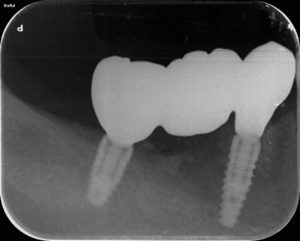

こんにちは!中津まさデンタルクリニックです。 こちらの患者様は、奥歯がなく噛みにくいとの主訴でした。 そのため、周りの歯を治療したあとにインプラントを埋入し奥歯で噛みやすい環境をつくりました。 症例によっては長期の治療に […]